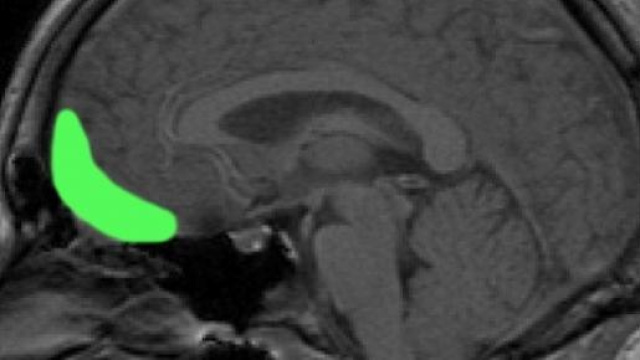

L'area di corteccia cerebrale denominata orbitofrontale laterale, che si trova grossomodo in corrispondenza dell'arcata sopracciliare, influirebbe in maniera determinante sulla scelta dei candidati da votare alle elezioni. Lo suggerisce uno studio condotto da un gruppo di ricercatori del prestigioso Montreal Neurological Institute, nella città di Montreal, in Québec, Canada.

Numerosi studi indicano che la corteccia orbitofrontale è implicata sia nel giudizio di aspetti sociali del comportamento sia nelle decisioni di carattere economico o finanziario. "La nostra ricerca" conclude Leslie Fellows "indica che la porzione più laterale di quest'area del cervello è necessaria per porre in relazione il giudizio sociale di una persona, basato sul suo aspetto esteriore, con la decisione di votare quella persona alle elezioni".